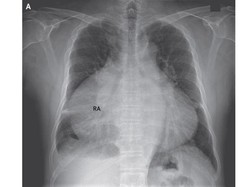

Karena Kondisi Tak Lazim, 80 Persen Dada Pria ini Tertutup Jantung

Pria ini datang ke rumah sakit dalam keadaan kaki dan tangan membengkak. Tak tahunya ada yang aneh dengan jantungnya.